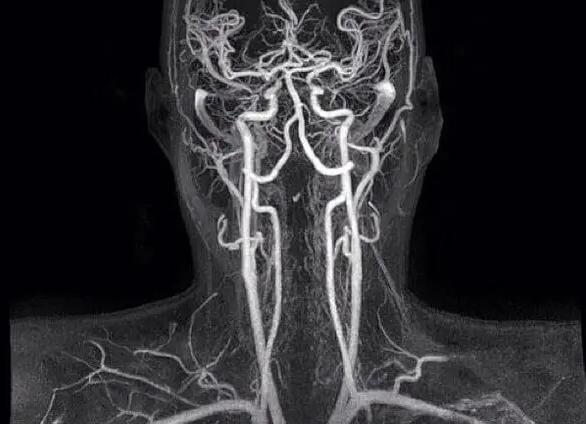

Для диагностики спазмов, необходимо пройти полное обследование всего шейного отдела, то есть сделать рентген и магнитно-резонансное обследование. Дуплексное сканирование выполняется для обнаружения бляшек и тромбов. Также хорошо будет сделать МРТ с введением контрастного вещества.

- Магнитно-резонансная томография — дополняется контрастированием, что позволяет выявлять любые нарушения строения и функции сосудов.

- Дуплексное сканирование — определяется скорость кровотока, наличие тромбов и атеросклеротических бляшек.

- Рентгенография — проводится в тех ситуациях, когда отсутствует техническая возможность выполнить МРТ.